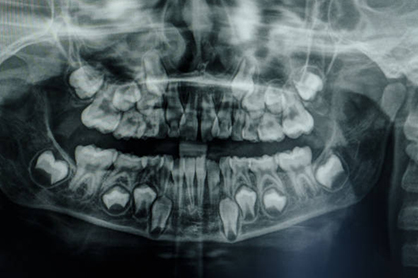

Severe Bone Loss

Difficult Cases

- We treat patients when other providers cannot manage.